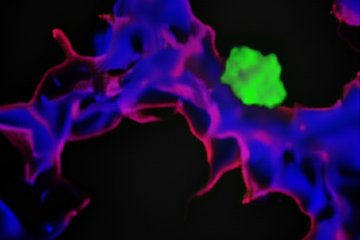

Aber welche molekularen Prozesse werden durch Spleißproteine gesteuert? „Unsere Studien haben gezeigt, dass RBPMS und RBPMS2 eine Schlüsselrolle bei mehreren grundlegenden Prozessen der Herzentwicklung spielen”, so Lin. Die Gruppe entdeckte, dass RBPMS und RBPMS2 nicht nur die Bildung von Isoformen für Proteine des Sarkomers steuern, sondern auch die Bildung des Spindelapparats regulieren, der für die Zellteilung unerlässlich ist. „Wenn beide Proteine inaktiv sind, ist die Zellteilung gestört“, erklärt Lin.